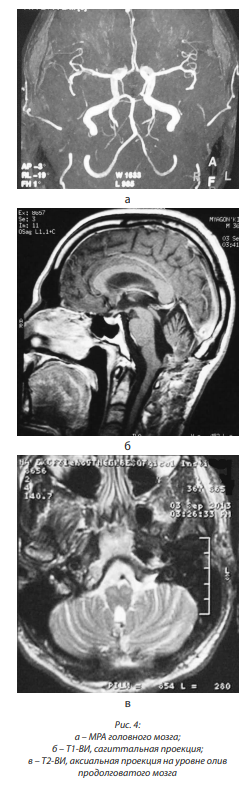

При МРА от октября 2012 г.: сужений, аневризм, патологической извитости магистральных артерий не выявлено; вариант отхождения левой задней мозговой артерии (ЗМА), сосудистая связь с каверномой отсутствует (рис. 2, а, б, в, г, д).

В сентябре 2013 г. МРТ головного мозга выявила симметричную, бивентрикулярную водянку; рубцово-глиозные изменения в области миндаликов мозжечка справа; отсутствие патологического накопления контрастного вещества, отсутствие расширения оболочечных пространств полушарий мозга; без динамики по сравнению с МРТ от декабря 2012 г. Не описаны имевшиеся признаки ГДО. МРА дополнительной сосудистой сети не выявила (рис. 4, а, б, в).